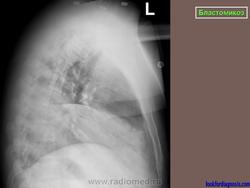

Рентгенологически отмечаются выраженные изменения лимфатических узлов средостения, очаговые инфильтраты, в некоторых из них развиваются каверны с неправильными контурами. При диссеминации процесс захватывает многие органы, эти формы часто заканчиваются гибелью больного.